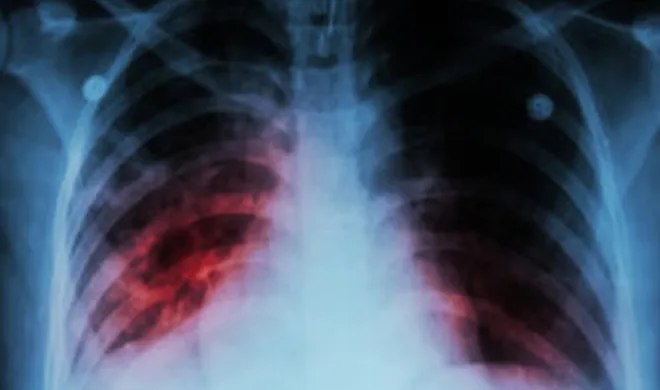

World Tuberculosis Day, विश्व टीबी दिवस: इस बीमारी से हर साल मरते हैं लाखों लोग, जानिए इसके लक्षण

टीबी यानि क्षय रोग से देश के लाखों लोग हर साल मर जाते हैं। सबसे आश्चर्य की बात यह है कि इस बीमारी का इलाज होते हुए भी हर सालों लाखों लोग इसका शिकार हो जाते हैं। आजादी के इतने साल भी अभी तक भारत को टीबी मुक्त नहीं करवाया जा सका है।

हेल्थ डेस्क: टीबी यानि क्षय रोग से देश के लाखों लोग हर साल मर जाते हैं। सबसे आश्चर्य की बात यह है कि इस बीमारी का इलाज होते हुए भी हर सालों लाखों लोग इसका शिकार हो जाते हैं। आजादी के इतने साल भी अभी तक भारत को टीबी मुक्त नहीं करवाया जा सका है।